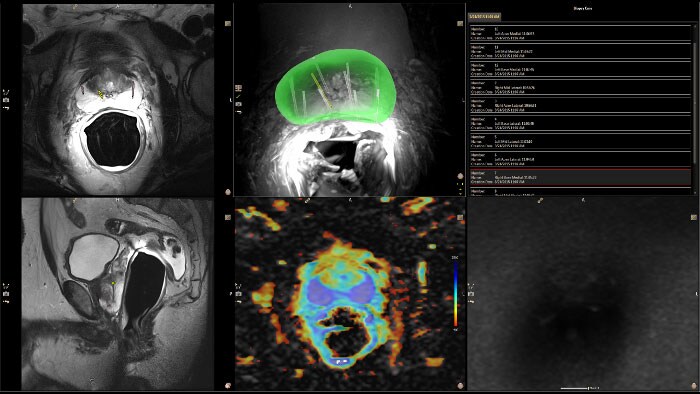

Invivo DynaCAD Prostate

Inclui uma segmentação de glândulas com base em modelos, que efetua automaticamente uma segmentação 3D, delineando o interior central e o exterior periférico da glândula prostática. Pergunte ao seu consultor sobre a disponibilidade em seu país.